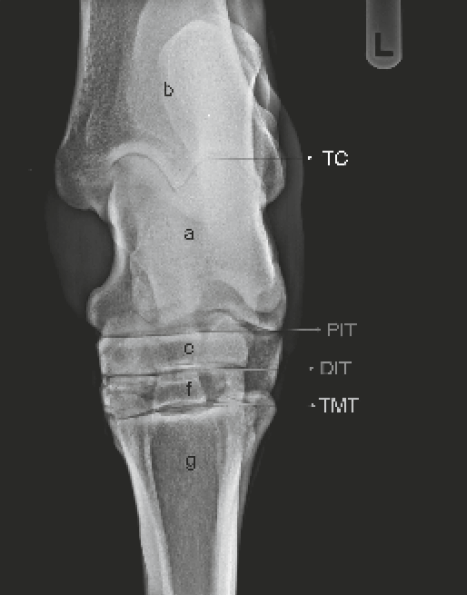

Spat

Spat is een benige verdikking aan de binnen onderkant van het spronggewricht. Spat is een uiting van arthrose, namelijk van de kleine gewrichten onder in de sprong. Ook hier wordt de verdikking veroorzaakt door nieuwe bot vorming. Zeker in het acute stadium veroorzaakt spat kreupelheid. Spat ontstaat door trauma, overbelasting, erfelijke aanleg en verkeerde beenstand.

Symptomen van Spat

Symptomen van spat zijn:

• Lichte stijfheid, dit gaat vaak ongemerkt

• Geleidelijk aan kreupel

• Harde zwelling op het spronggewricht

• Ophoping van vocht rondom de zwelling

Bolspat

Bolspat is een overvulling van het spronggewricht. Het is te zien als een zachte zwelling aan de voor binnenzijde van de sprong, en vaak ook aan de buiten bovenkant. De bolspat kan ontstaan door acute overbelasting of door trauma, aar het kan ook het gevolg zijn van een chronische overbelasting. Een degeneratieve beschadiging van het gewrichtskraakbeen in het spronggewricht is vaak de achterliggende oorzaak van een bolspat. De aandoening is erfelijk.

Symptomen van bolspat

Bij bolspat zie je een verdikking op de binnenzijde en/of de buiten bovenkant van de sprong. Deze verdikking is zacht en kan zowel langzaam als acuut zijn ontstaan.